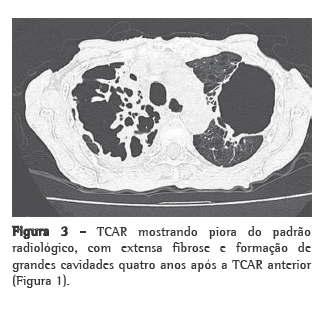

Encontrava-se em uso de levotiroxina, calcitriol e prednisona 15 mg/dia, mas já havia feito uso de metotrexato previamente. Ao exame físico, apresentava-se emagrecida (30 kg de peso e índice de massa corpórea de 14 kg/m2), sem linfonodomegalia cervical ou supraclavicular e sem baqueteamento digital. A ausculta pulmonar revelou apenas murmúrio vesicular reduzido difusamente. A radiografia de tórax no início do quadro, há 4 anos, mostrava hiperinsuflação pulmonar e redução importante da trama vascular nas metades superiores de ambos os campos pulmonares (Figura 1), e a TCAR realizada revelara enfisema parasseptal, cavidades e destruição do parênquima com predomínio nos lobos superiores (Figura 2). A gasometria arterial e o teste tuberculínico não revelaram anormalidades. A espirometria mostrou distúrbio ventilatório obstrutivo incipiente, sendo iniciado tratamento com formoterol. No último ano, com a piora dos sintomas, a paciente foi submetida à nova TCAR, que mostrou piora do padrão radiológico (Figura 3). A baciloscopia direta do escarro foi negativa para BAAR. O método Gomori-Grocott com prata metenamina evidenciou formas leveduriformes intracelulares, e as culturas das amostras de escarro e do lavado broncoalveolar em ágar dextrose Sabouraud revelaram a presença de Histoplasma capsulatum. Foi iniciado tratamento com itraconazol, 200 mg/dia.(8) A paciente encontra-se em acompanhamento ambulatorial com melhora sintomática e aumento de peso.

O aspecto radiológico da lesão inicial ­caracteriza-se por infiltrado inflamatório intersticial localizado, adjacente às bolhas enfisematosas, e frequentemente acometendo os segmentos apicais e apicoposteriores dos lobos superiores.(2,5,6,10) É comum que haja espessamento das paredes das bolhas com subsequente necrose e aumento da fibrose levando à perda de volume pulmonar. Esse processo contínuo culmina na formação de cavidades grandes e persistentes que podem ocupar o espaço de todo um lobo.(10) A disseminação de material fúngico para porções pulmonares pendentes pode ser o mecanismo de desenvolvimento de fibrose intersticial nos lobos inferiores por criação de novos focos inflamatórios.(4,10) Adenopatias mediastinais não são observadas nessa forma clínica, o que diferencia a HPCC de outras doenças granulomatosas, como a sarcoidose.(4,14)